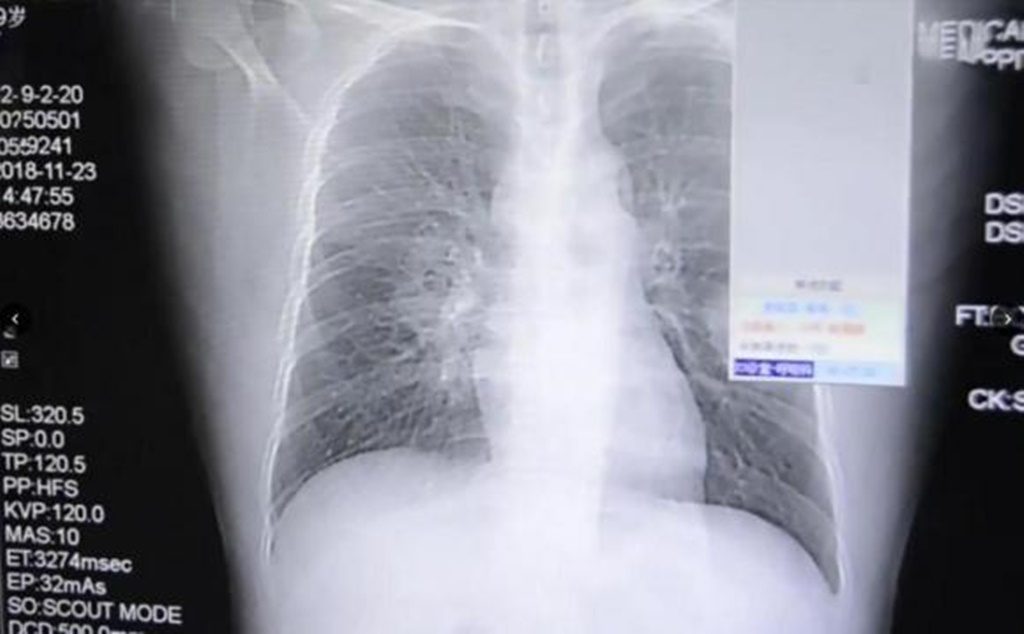

Un bărbat a ajuns la spital cu o infecție fungică severă la plămâni provocată de un obicei respingător pentru mulți și deloc igienic. Bărbatul făcuse o obsesie din a-și mirosi șosetele la sfârșitul zilei. Iar acest obicei l-a adus la spital.

Bărbatul din China a povestit că obișnuiește ca atunci când ajunge acasă, după o zi de muncă, să se schimbe în haine mai confortabile, să își scoată șosetele pe care le miroase îndelung. Medicii sunt de părere că acest obicei este și cel care i-a provocat o gravă infecție pulmonară, scrie The Sun.

Explicația dată de specialiști este că bărbatul avea o ciupercă pe picior, microbul fiind transmis prin nas spre plămâni.

Bărbatul din Zhangzhou, provincia Fujian din sud-estul Chinei, a fost internat și urmează un tratament. Medicii spun că infecția este tratabilă, însă îi recomandă bărbatului să renunțe la obiceiul său.